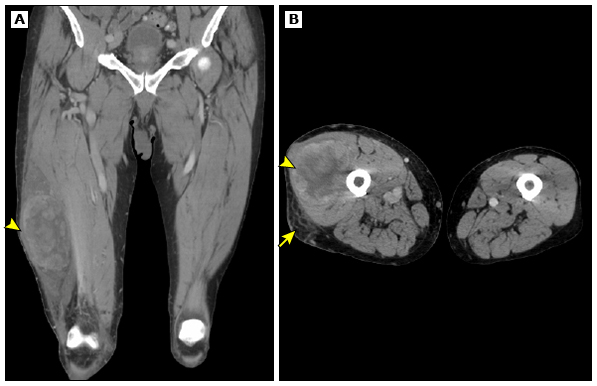

При проведении КТ делается множество рентгеновских снимков одной и той же части тела под разными углами, которые затем объединяются с помощью компьютерной технологии. КТ  работает так же эффективно, как и МРТ для исследования мягких тканей: преимущественно в брюшной полости, внутренностях или забрюшинном пространстве.

КТ органов грудной клетки — стандартное исследование для выявления метастазов в легких у всех пациентов с саркомой мягких тканей.

КТ мягкотканной саркомы бедра. Источник изображения: UpToDate, “Clinical presentation, diagnostic evaluation, and staging of soft tissue sarcoma”